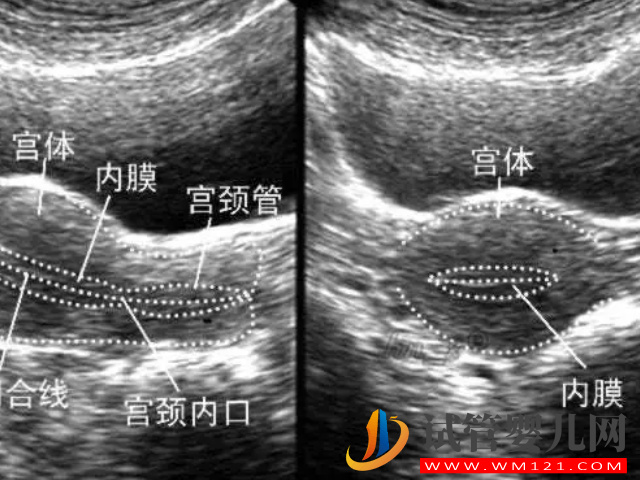

上面就是不同階段的參考值,而最佳懷孕以及做試管嬰兒的厚度是在8mm-12mm之間,如果說低于這個范圍就可能導致胚胎著床不穩(wěn)定,或者是根本沒有著床的可能性。但是,子宮內(nèi)膜并非是肉眼可見的,很多時候需要通過專業(yè)的專業(yè)檢查,綜合性評斷才能確保其結果的準確度。

子宮內(nèi)膜的厚度是會隨著月經(jīng)周期發(fā)生變化的,所以在每個階段檢查的參考值可能是不一樣的,而在臨床上面可以通過臨床變現(xiàn)和陰超檢測排判斷自己是否是子宮內(nèi)膜過薄。

2、陰超檢測

其實現(xiàn)目前準確定的判斷你是否有子宮內(nèi)膜薄的情況,其最主要的就是通過超聲檢查,如果說在檢查下發(fā)現(xiàn)自己內(nèi)膜的厚度并非沒有達到合適的范圍,低于就是過薄,高于就是過厚,都是不利于身心健康的。